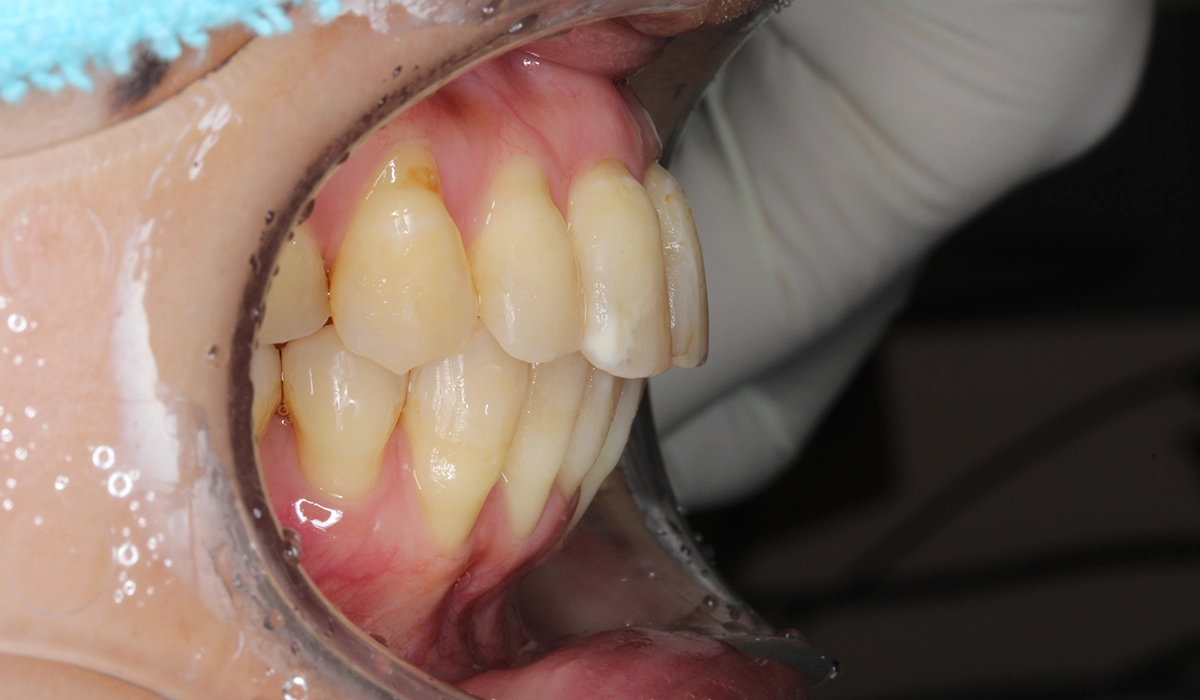

術前:右側

術後:右側